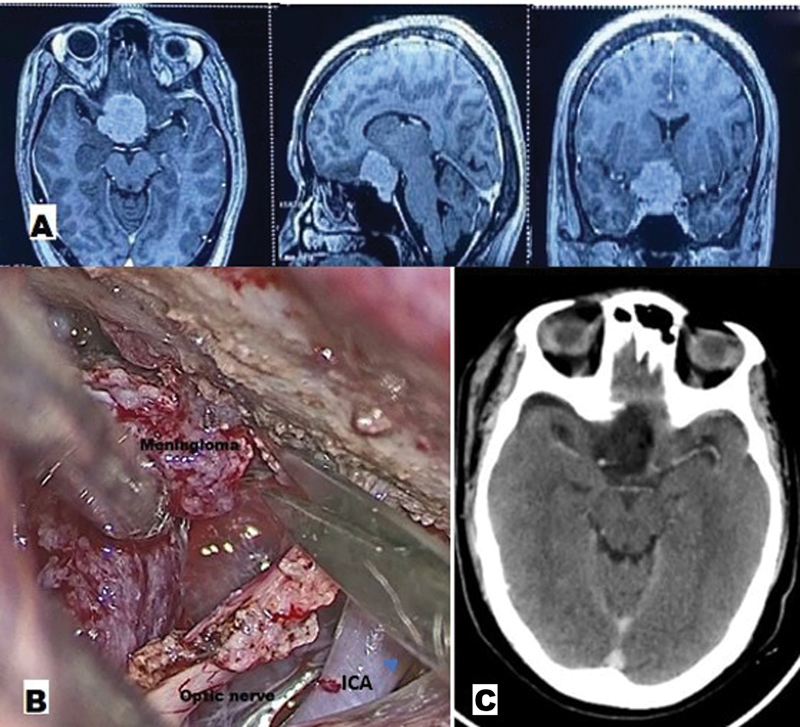

Background  In recent times, the supraorbital approach via eyebrow incision has gained tremendous popularity in targeting the anterior skull base and few middle cranial fossa lesions, over the more traditional pterional and frontotemporal approaches. However, the extremely narrow viewing angle through this approach requires frequent adjustments of the operating table and microscope for optimal visualization. Illumination via such a small opening in such deep-seated location was another limiting factor. Keeping these problems and cumbersomeness of microscope in mind, experienced surgeons gradually shifted over to purely endoscopic or endoscope-assisted supraorbital keyhole approaches. But it was also limited due to high cost, steep learning curve, and difficulties faced in blood-filled cavities. To circumvent these limitations of the microscope and endoscope, the supraorbital keyhole approach can be accomplished with an exoscope (ExSOKHA). Although various cranial procedures using exoscope have become well established in contemporary times, there is paucity of studies and literature dedicated specifically to this minimally invasive supraorbital keyhole approach using the exoscope only. Here, we aim to study the feasibility and usefulness of the exoscope in targeting skull base lesions via the supraorbital keyhole approach to determine if it can be used in learning while transitioning from the microscope to the endoscope, with the primary objective being the user friendliness of the exoscope in the SOKHA technique. Materials and Methods  This prospective observational study was conducted in the department of neurosurgery over a period of 7 years. The sample size was 50. The study utilized an exoscope and support arm-2D VITOM rigid-lens telescope (Model 28095 VA, Karl Storz Endoscopy, Tuttlingen, Germany) with a 10-mm outer diameter and a shaft length of 14 cm, light source (Xenon Nova 300, Karl Storz GmBH and Co., Tuttlingen, Germany), camera head, video display monitor, and a holding arm. Results  Out of 50 cases, the majority were pituitary adenomas (30%) and meningiomas (38%), with aneurysms comprising 6%; only 4 cases (8%) had inadvertent frontal sinus opening and 2 cases (4%) had postoperative cerebrospinal fluid (CSF) leak. The duration of surgery ranged from 2 to 4 hours, with the shortest being for aneurysm clipping/CSF rhinorrhea and the longest for meningioma and pituitary adenoma excision. Intraoperatively, exoscope repositioning for adjustment was required for a maximum of nine times, which significantly reduced the overall operative time. Eight cases had near total excision; the remaining tumors had complete excision and the aneurysms had complete clipping. Hospital stay ranged from 4 to 7 days, with mean intensive care unit (ICU) stay of 3 days. None of the patients had any surgical cosmetic deformity. The Glasgow Outcome Scale of all patients was good (4/5 or 5/5). Thus, ExSOKHA offered good results in terms of operative time, frequency of adjustments, completeness of excision and clipping, and recurrence. The results were also comparable for other parameters like inadvertent frontal sinus violation, postoperative CSF leak, hospital stay, cosmetic deformity, and outcome. Conclusion  The exoscope is a further advancement in the telescopic system, which provides a higher focal length (250-550 mm), ergonomically superior surgery with better depth illumination in skull base lesions approached via the supraorbital keyhole approach, significantly reducing operative time and improving resection margins due to increased corner visibility and easy maneuverability. It helps learn neuroendoscopy with the familiar principles of microneurosurgery, possibly shortening the learning curves. It bridges the gap between the endoscope and the microscope as the surgery is performed while viewing the screen (as in endoscope), but without needing to take the scope inside the operative field (as in microscope), making it easier to maneuver while also limiting space occupancy.